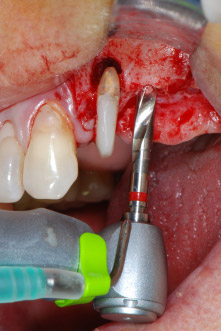

Имплантологичното ложе е подготвено в позиции 25 и 26 с ротиращи инструменти, използвайки обратен наконечник 20:1 с усъвършенстван и мощен имплантологичен мотор (Implantmed, W&H) (Фиг. 8).

Следващата препарация близо до синуса отново е извършена с пиезохирургичен накрайник (Piezomed, накрайник S2).

Имплантологичното ложе е обработено с новия имплантологичен мотор (Фиг. 20), в комбинация с обратен наконечник, специално проектиран за орална хирургия и имплантология.

Предавателното съотношение20:1 заедно с високия въртящ момент до 6.2 Ncm осигуряват препарация на ниски обороти, поставяне на имплант и рязане. Финалната препарация близо до мембраната на синуса отново е извършена с пиезоелектрически апарат и накрайник със сферичен диамантен връх.